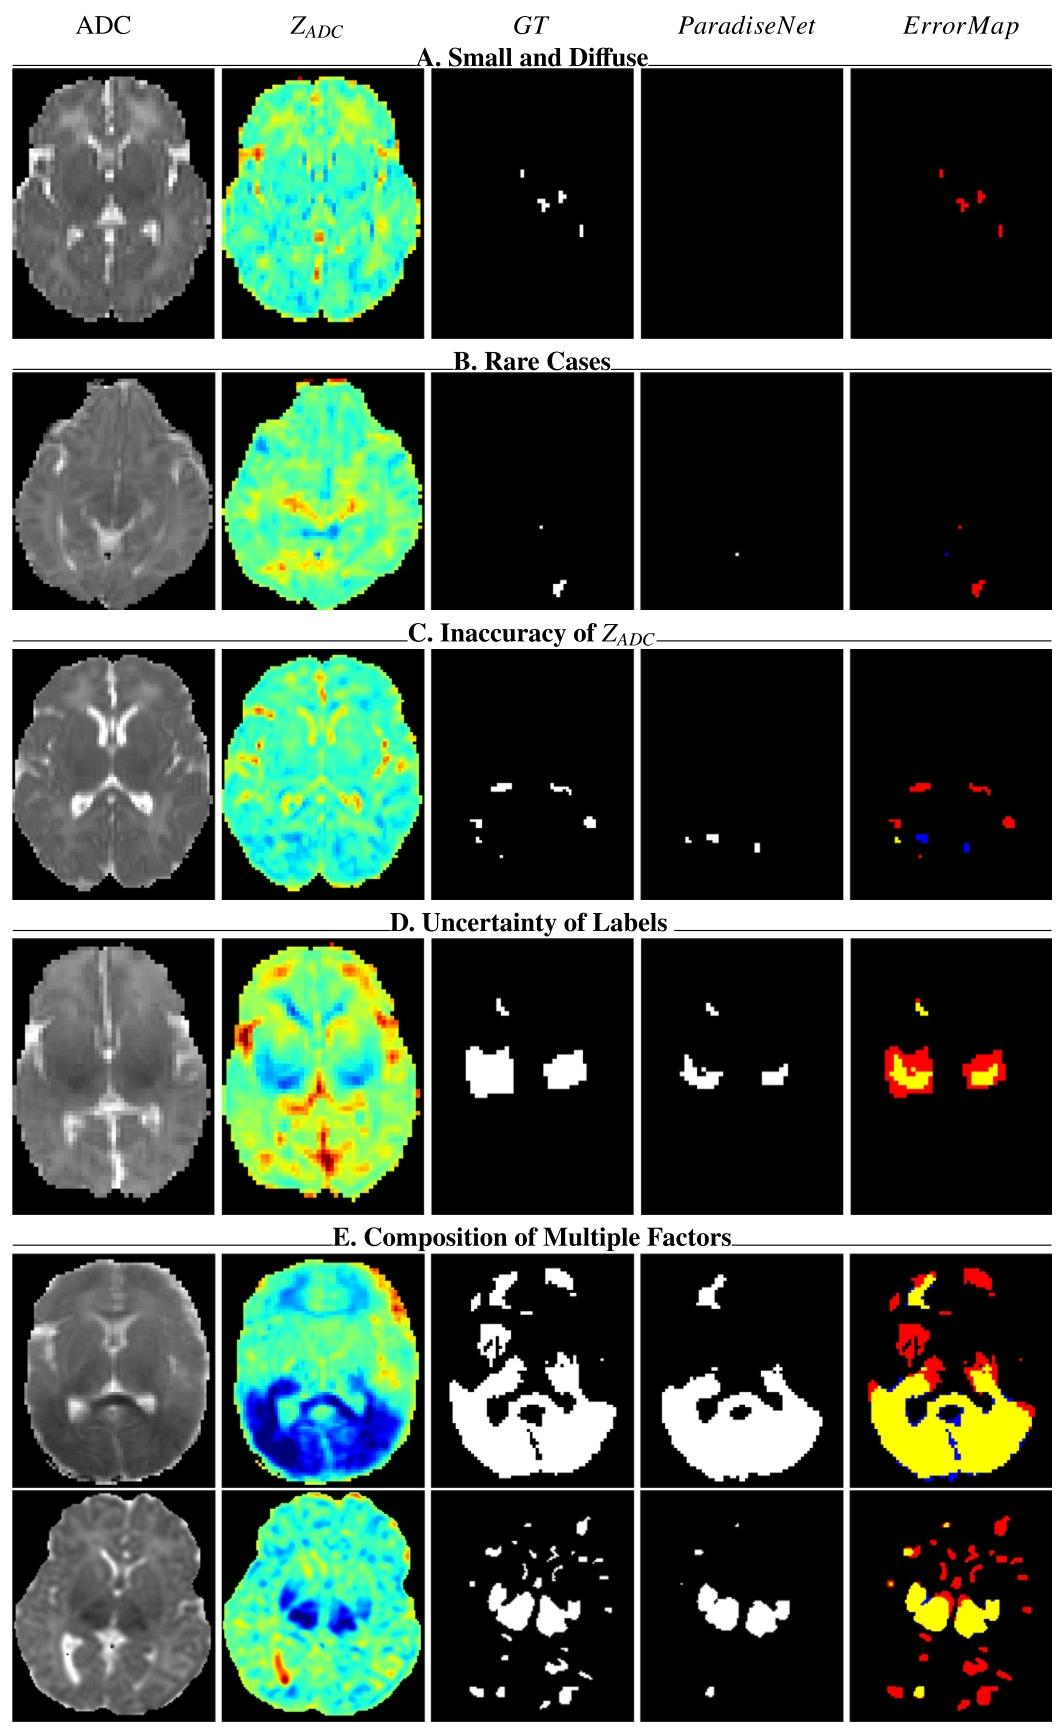

5.1. Comparisons with STOA general algorithms ParadiseNet consistently achieves state-of-the-art performance on small diffuse lesion segmentation. In our study, we comparedParadiseNet with widely-utilized deep learning architectures in medical imaging. The results are summarized in Table 2, under two distinct settings: the whole dataset, where evaluation metrics are calculated across the entire dataset to measure overall quality, and small diffuse lesion cases, where metrics are specifically computed for patients with small diffuse lesions (lesion percentage less than 1% and 2%). Compared to existing methods, our model demonstrates superior performance, particularly in small diffuse lesion regions, highlighting its efficacy in addressing this challenging detection task. (1) Whole dataset setting: As indicated in Table 2, ParadiseNet achieves a mean Dice coefficient of 0.61, which is a 3% increase over the closest competing methods in the whole dataset for lesion region prediction accuracy. Moreover, it shows a notable improvement in NSD, with a mean of 0.72, corresponding to a 2% enhancement in boundary prediction accuracy compared to other UNet variants. The sensitivity of ParadiseNet is remarkable, with a mean of 0.64, reinforcing its ability to detect true positives effectively. Simultaneously, its specificity remains exceptionally high at a mean of 0.9989, indicating a low rate of false positives in lesion identification. (2) On small diffuse lesions: Notably, ParadiseNet exhibits significant improvements in small diffuse lesion cases, especially with a Dice increase of 5% and NSD of 5% for lesions less than 1% over nnUNet, and a Dice and NSD increase of 4% for lesions less than 2% with most methods. These results underscore ParadiseNet’s capability in managing unbalanced data distribution and its precision in delineating lesion boundaries for small diffuse lesions. The predictive performances of different methods are also visually presented in Fig. 5. We visualized slices from different patients, each displaying various lesioned areas. The Dice and NSD metrics for the whole brain volume are displayed beneath each image. These visualizations clearly demonstrate that ParadiseNet significantly and consistently outperforms in terms of Dice and NSD metrics.

5.1 与最先进通用算法的比较 ParadiseNet在微小弥散性病变分割任务中持续实现了最先进的性能。在本研究中,我们将ParadiseNet与医学影像中广泛使用的深度学习架构进行了比较。结果总结于表2,分为两种不同场景:全数据集场景(计算整个数据集的评估指标以衡量整体性能)和微小弥散性病变场景(专门针对病变占比小于1%和2%的患者计算指标)。与现有方法相比,我们的模型表现出更优的性能,尤其在微小弥散性病变区域,突显了其应对这一挑战性检测任务的有效性。 #### (1)全数据集场景 如表2所示,ParadiseNet的平均Dice系数达0.61,相比全数据集中最接近的竞争方法,病变区域预测准确率提升了3%。此外,其归一化表面距离(NSD)显著改善,平均值为0.72,相比其他UNet变体,边界预测准确率提升了2%。ParadiseNet的敏感性表现卓越,平均值为0.64,证实了其有效检测真阳性病变的能力。同时,其特异性维持在极高水平,平均值为0.9989,表明病变识别中的假阳性率极低。 (2)微小弥散性病变场景 值得注意的是,ParadiseNet在微小弥散性病变病例中表现出显著改进:对于占比小于1%的病变,其Dice系数相比nnUNet提升5%,NSD提升5%;对于小于2%的病变,相比大多数方法,Dice和NSD均提升4%。这些结果凸显了ParadiseNet在处理数据分布不平衡问题上的能力,以及在勾勒微小弥散性病变边界时的精确性。 不同方法的预测性能也在图5中进行了可视化展示。我们选取了不同患者的切片,每例显示不同的病变区域,图像下方标注了全脑体积的Dice和NSD指标。这些可视化结果清晰表明,ParadiseNet在Dice和NSD指标上显著且持续优于其他方法。

Fig. 5. Lesion segmentation results of different methods. Each row is a patient with different percentages of the brain being lesioned. Compared with existing methods, ParadiseNet higher accuracy in lesion regions with different percentage.

图5. 不同方法的病变分割结果。每行展示一位脑损伤占比不同的患者。与现有方法相比,ParadiseNet在不同损伤比例的病变区域中均表现出更高的准确性。

Fig. 7. Failure cases in HIE. Yellow indicates true positives, red denotes false negatives, and blue denotes false positives.

图 7. HIE 分割失败案例。黄色表示真阳性(正确检测的病变),红色表示假阴性(漏检的病变),蓝色表示假阳性(误检的正常区域)。